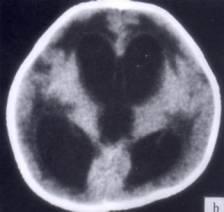

病历摘要:??患者女性,10岁。结核性脑膜炎愈后8月,头痛伴恶心呕吐1周,并渐加重。体检:神清,精神差,反应迟钝,双眼底视神经乳头水肿,双眼外展差,余未见...

问题 病历摘要:??患者女性,10岁。结核性脑膜炎愈后8月,头痛伴恶心呕吐1周,并渐加重。体检:神清,精神差,反应迟钝,双眼底视神经乳头水肿,双眼外展差,余未见明显异常。 下列关于脑脊液的叙述哪些是正确的?